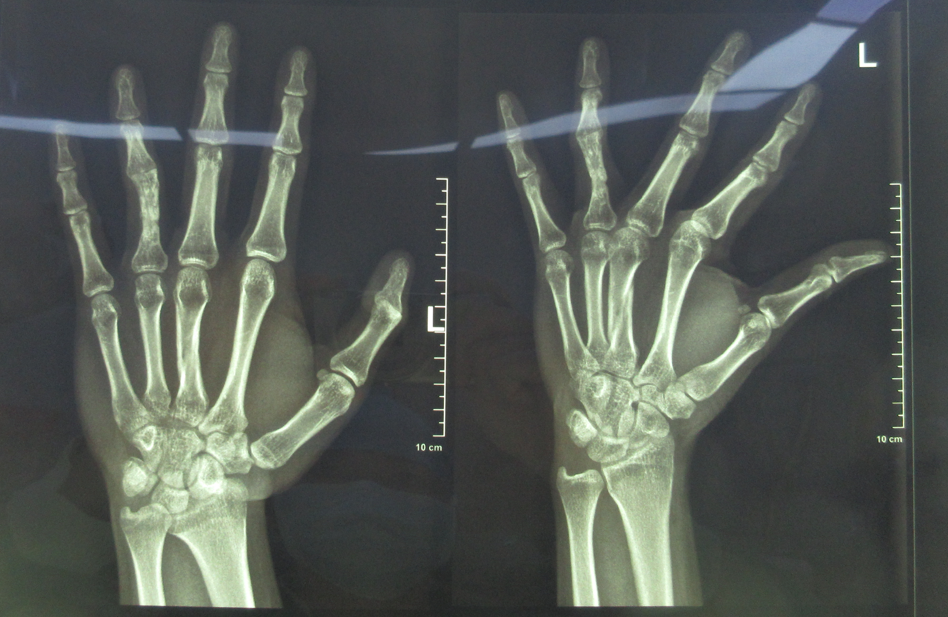

術(shù)前X光片

“當(dāng)時他的環(huán)指近節(jié)見多處手術(shù)疤痕,環(huán)指尺偏畸形,近指間關(guān)節(jié)屈曲30°畸形,活動度為零,可以判斷是環(huán)指骨折術(shù)后長時間制動導(dǎo)致的關(guān)節(jié)屈曲攣縮畸形,檢查發(fā)現(xiàn),環(huán)指關(guān)節(jié)面完整,能被動活動,我們認為可以進行關(guān)節(jié)肌腱松解術(shù),恢復(fù)手指功能。”有著多年手外科臨床經(jīng)驗的王小立主任說。